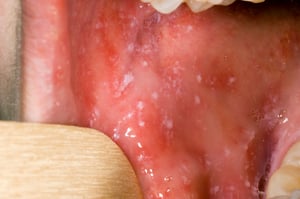

Las manchas de Koplik de la mucosa bucal se asemejan a granos de arena blanca rodeados de areolas rojas. Estos enantemas son patognomónicos y aparecen en el 70% de los pacientes (2). Las manchas de Koplik aparecen durante el pródromo antes del inicio del exantema, en general en la mucosa oral opuesta al primer y segundo molares superiores. Estas manchas pueden ser extensas y producir un eritema moteado difuso en la mucosa oral.

Las manchas de Koplik se describen clásicamente como máculas rojas brillantes con centros blancos o azul-blanquecino que se parecen granos de arena. Pueden aparecer en cualquier lugar de la boca, en general preceden al exantema y son patognomónicas del sarampión.

Images courtesy of the Public Health Image Library of the Centers for Disease Control and Prevention.